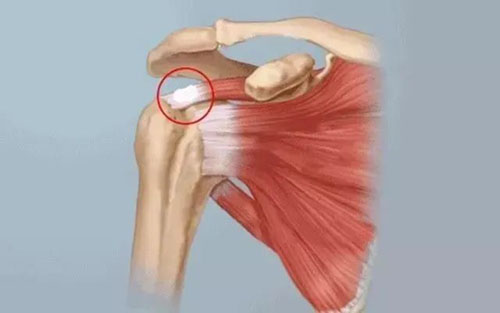

一、什么是肩袖钙化性肌腱炎?

肩袖钙化性肌腱炎是一种由于钙盐在肩袖肌腱中沉积引起关节周围炎症反应的疾病,好发于40-60岁的女性患者,其具体发病机制尚不清楚。

钙化性肌腱炎属于自限性疾病,非手术治疗为治疗该疾病的首选方法,经严格非手术治疗无效者可考虑采用手术治疗。